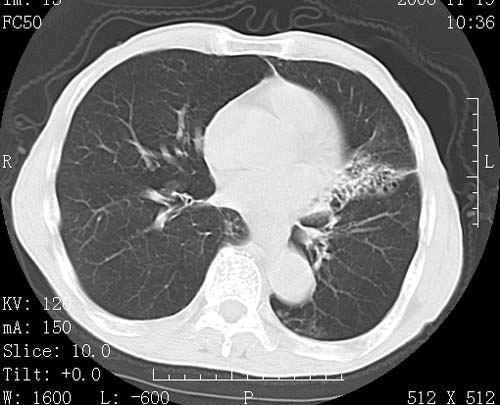

标题: CT16691:m 67 胃镜确诊食管下段及贲门癌 [打印本页]

标题: CT16691:m 67 胃镜确诊食管下段及贲门癌

术前查体,双肺部结节是转移?结核?请点评

1)符合食管癌表现。2)两肺及纵隔淋巴结多发性转移瘤。3)左肺上叶舌段及两肺下叶炎症感染。

1)符合食管癌表现。2)两肺及纵隔淋巴结多发性转移瘤。3)左肺上叶舌段支气管扩张伴感染.

食管癌伴双肺转移,评述:肺部毛细血管网丰富,全身血液均快速流经肺部,癌细胞容易过滤定植,形成转移瘤,影象特点为以毛细血管末梢为中心的结节灶,边缘光滑锐利,少见有中心空洞着,不同来源的转移瘤可有各自特点,如甲状腺癌为双肺弥漫性微结节,本例有原发灶,双肺影象灶典型,左肺舌段条带状网格样伴胸膜天幕征,可视为癌性淋巴管炎。

1)符合食管癌表现。2)两肺及纵隔淋巴结多发性转移瘤。3)左肺上叶舌段支气管扩张伴感染